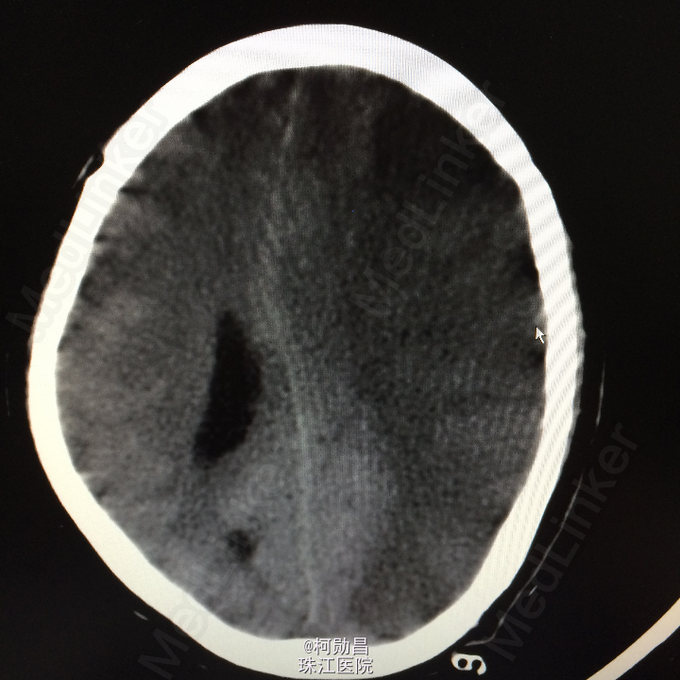

查体:神志呈昏睡状态,言语不能,精神差,双侧瞳孔不等大,左侧3mm,对光反射消失;右侧瞳孔2,mm,对光反射灵敏,右侧肢体肌力0级,左侧肢体肌力5级,右侧肢体肌张力减低,余未见异常。 辅助检查:左侧大脑半球累计岛叶、基底节区(以颞顶叶为主)大片状低密度影,考虑脑梗塞;中线结构明显右移。